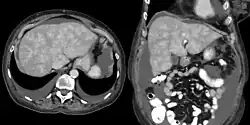

Congestive hepatopathy is liver dysfunction due to venous congestion, usually due to congestive heart failure. The gross pathological appearance of a liver affected by chronic passive congestion is "speckled" like a grated nutmeg kernel; the dark spots represent the dilated and congested hepatic venules and small hepatic veins. The paler areas are unaffected surrounding liver tissue. When severe and longstanding, hepatic congestion can lead to fibrosis; if congestion is due to right heart failure, it is called cardiac cirrhosis.[1]

Increased pressure in the sublobular branches of the hepatic veins causes an engorgement of venous blood, and is most frequently due to chronic cardiac lesions, especially those affecting the right heart (e.g., right-sided heart failure), the blood being dammed back in the inferior vena cava and hepatic veins. Central regions of the hepatic lobules are red–brown and stand out against the non-congested, tan-coloured liver. Centrilobular necrosis occurs.[2]

Macroscopically, the liver has a pale and spotty appearance in affected areas, as stasis of the blood causes pericentral hepatocytes (liver cells surrounding the central venule of the liver) to become deoxygenated compared to the relatively better-oxygenated periportal hepatocytes adjacent to the hepatic arterioles. This retardation of the blood also occurs in lung lesions, such as chronic interstitial pneumonia, pleural effusions, and intrathoracic tumors.